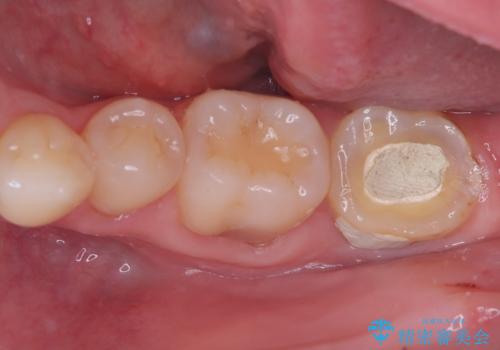

右の奥歯を機能回復|再根管治療とインプラントでしっかり噛める歯へ